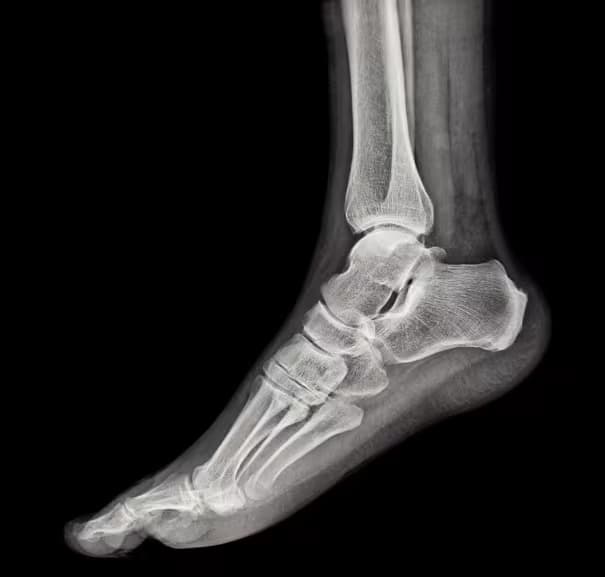

Calcaneus Projections

Calcaneus Projections Patient Preparation Explain the procedure to the patient.. Remove shoes, socks, and metallic objects from the foot and ankle region.. Ensure patient comfort and correct positioning.. Use lead shielding where applicable.. --- BASIC PROJECTIONS Plantodorsal (Axial) Projection — ...

Read more →